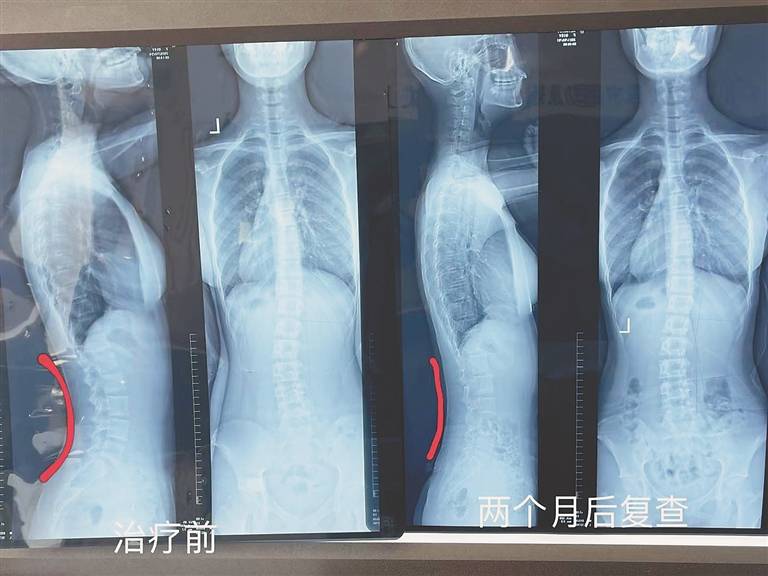

x光片(治疗前): 医师诊断:胸腰段s型脊柱侧弯15° 治疗方法:脊柱功能